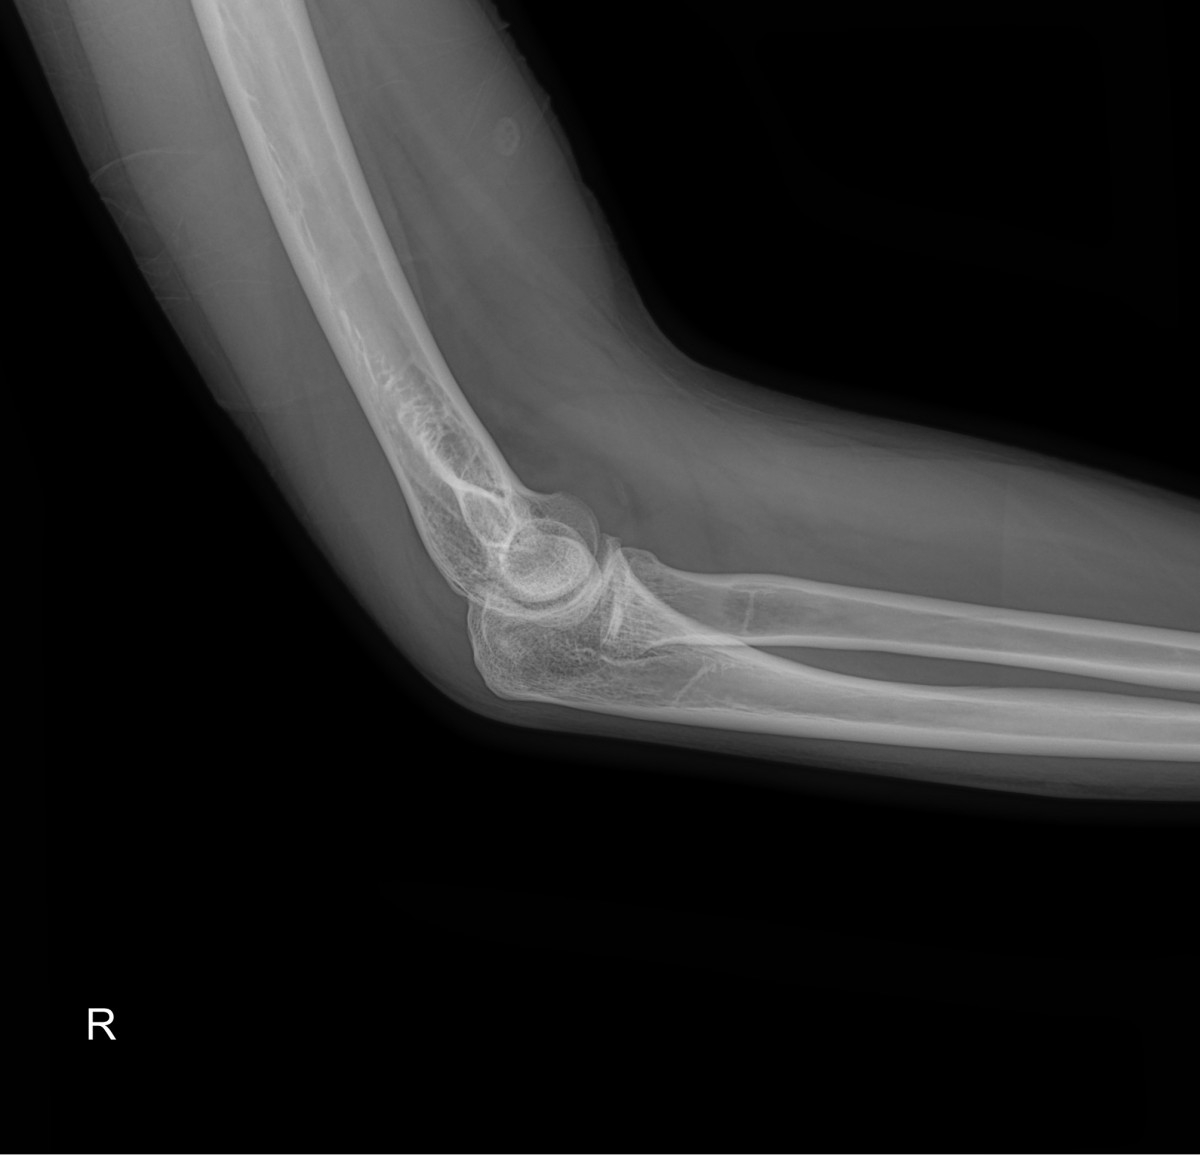

이재상원장님 팔꿈치 골절 수술 김시O 환자

dae765e4d9ac96aee867c9d6292d8784_1758001848_761.jpg